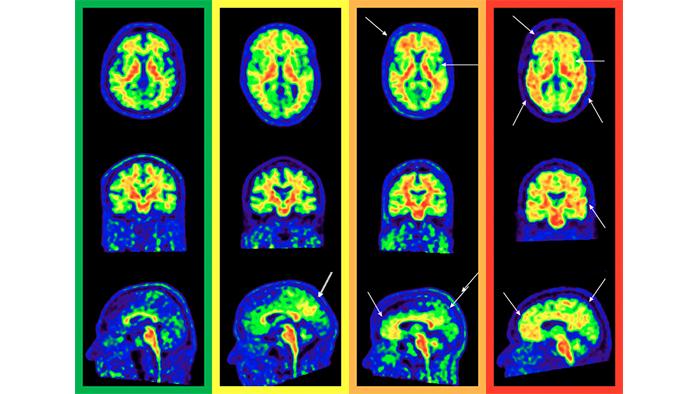

*Imagen - Ejemplo de PET cerebrales de amiloide de diferente clasificación patológica según la medida visual propuesta en el estudio (verde: sin patología; amarillo, grado 1; naranja: grado 2; rojo: grado 3). Las flechas indican la extensión de la patología en los diferentes niveles.

En el ámbito de la investigación, esta prueba proporciona una gran cantidad de información sobre la presencia y extensión de estas placas, y permite cuantificar numéricamente, con una escala llamada Centiloid, qué grado de afectación tiene el participante o paciente. En cambio, en el ámbito clínico, los profesionales hacen una lectura visual de las imágenes, de carácter exclusivamente cualitativo, siguiendo unos protocolos establecidos que llevan hacia un único resultado: positivo o negativo.

Por su parte, la segunda coautora e investigadora del BBRC, Gemma Salvadó, destaca que “el trabajo en red ha permitido elaborar una serie de recomendaciones para detectar visualmente de forma más sencilla la acumulación de la proteína beta amiloide, y poder clasificar su extensión en regiones del cerebro que sabemos que están afectadas antes de la enfermedad de Alzheimer, como son el precúneo o el córtex orbitofrontal medial”.

Los investigadores del consorcio han compartido en acceso abierto este nuevo método, en el cual también explican cómo se podrían extrapolar los resultados a escala Centiloid utilizada en investigación, y detallan, por ejemplo, cuáles son las mejores orientaciones para detectar la extensión de la acumulación de amiloide en diferentes regiones del cerebro.